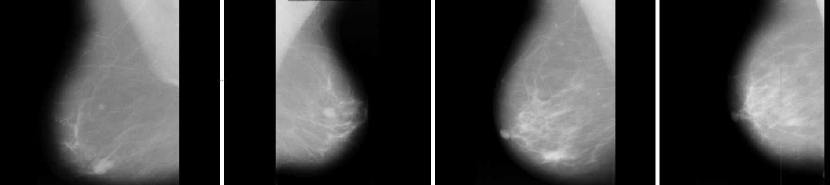

We use 100 mammographic images taken from ’Digital Database for Screening Mammography’ (DDSM) database released by the University of South Florida. 70 of the images are obtained from a healthy person and rest of them are taken from cancerous patient. We divide our database in two parts. 90 images are used to train our model and the 10 remaining images are used to test accuracy of our model.

Refer to caption

Figure 3: Cancer Images.

Figure 4: Normal Images.

There are some samples of cancer images in Figure 4 and normal images in Figure 4. We evaluate our attack success by observing decreasing accuracy of the CNN model. Adversarial samples which we generate mislead the model into making incorrect decision.